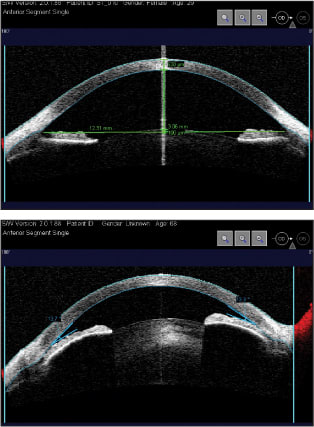

Figure 3. Top: Chamber depth and angle-to-angle distance. Bottom: Narrow angle (Visante, Carl Zeiss Meditec, Inc.).

Software tools in some of the systems also allow calculation of anterior chamber distance, angle-to-angle distance and other biometric measurements.3,7 Some clinicians also use AS-OCT to document flare and synechiae in the anterior chamber.